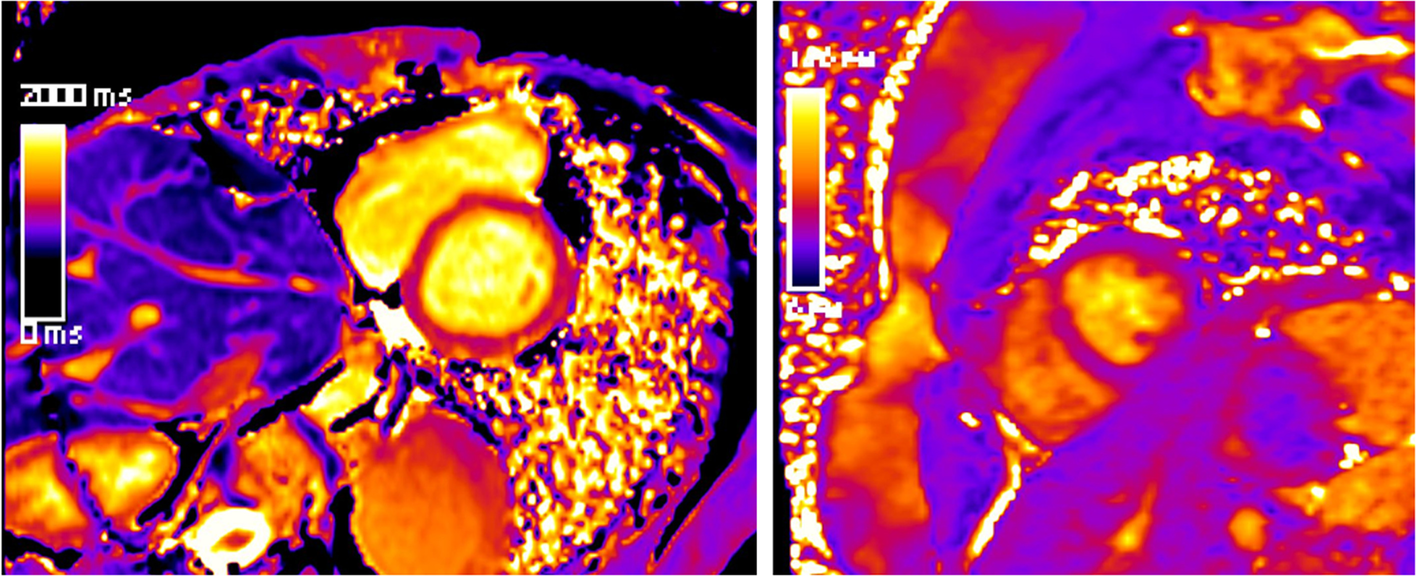

Mapping technologies and controversy about Gd contrast agent application

Mapping techniques are increasingly replacing traditional LGE and T2-weighted imaging (Fig. 7). Their advantages are manifold. Two main aspects are their inherent potential for quantification plus the concomitant effect of reduction of Gd contrast agents. This is important in the ongoing discussion of the potential harmful effects of Gd contrast agents.

Fig. 7

(Mapping technologies): qualitative (based on color maps) and quantitative (based on signal intensities) assessment is possible; in comparison to values of healthy cohorts, increased T2 values indicate myocardial edema and increased T1 values indicate fibrosis; here, healthy myocardium is depicted for SAX-T2- (left) and pre-contrast (“native”) T1 mapping (right) in midventricular position